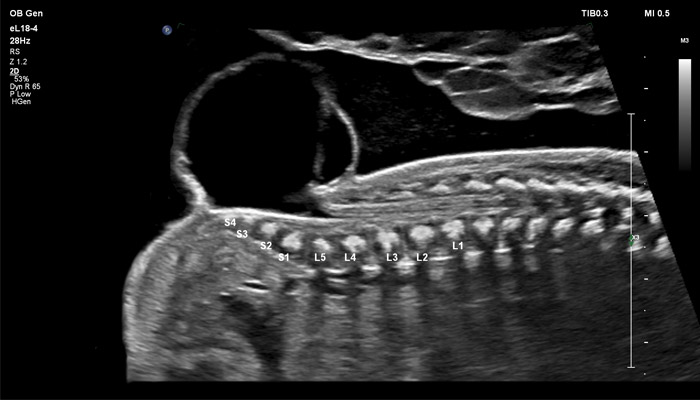

Начало новой жизни - это всегда особое время! Ультразвуковые решения Philips в области акушерства разработаны для того, чтобы позволить врачам сосредоточиться на здоровье каждой будущей мамы. Разработанные для обеспечения клиницистов дополнительной информацией ультразвуковые решения Philips позволяют получать не только детальную визуализацию анатомии плода уже в первом триместре, но и помогают оптимизировать рабочий процесс врача. Применение eL18-4 в I триместре беременности Сегодня ультразвуковая диагностика используется для выявления генетических аномалий, внутриутробных пороков, оценки жизнеспособности плода и определения срока беременности, как наиболее эффективный метод. Ультразвуковое исследование плода в первом триместре (до 13 недель 6 дней беременности включительно) является наиболее точным методом. В течение многих десятилетий трансвагинальный метод ультразвукового исследования был «золотым стандартом» диагностики в акушерстве. Сегодня линейный матричный датчик может стать альтернативой общепринятому трансвагинальному методу оценки состояния плода и репродуктивных органов женщины. Детальная анатомия плода и ранняя диагностика пороков в I триместре Ультразвуковое исследование является основным методом визуализации для оценки врожденных аномалий плода. Линейный матричный датчик eL18-4 позволяет получить детальную информацию об анатомии плода и выявить пороки на ранней стадии развития. Сверхширокополосная PureWave матрица датчика генерирует частоты в диапазоне 2-22 МГц, что формирует одинаково высокоинформативные, четкие изображения по всей глубине сканирования до 14 см.

До введения высокочастотных линейных датчиков точная ультразвуковая диагностика мочевой системы плода была доступна в основном после 16-17 недель беременности. Новая технология еL18-4 позволяет проводить раннюю морфологическую оценку плода уже в первом триместре. Клинический случай с применением eL18-4 демонстрирует, что кортико-медуллярная дифференцировка почек плода возможна на 14 неделе беременности”.

Использование линейного матричного датчика eL18-4 при осмотре беременных в I триместре, особенно на ранних сроках, позволяет ограничиться трансабдоминальным сканированием вместо трансвагинального и при этом получить максимально полную диагностическую информацию. Отсутствие полостного исследования чрезвычайно важно для соблюдения принципа ALARA – использования минимальной необходимой мощности для безопасности пациента. Благодаря применению мультичастотного датчика с диапазоном от 2 до 22 МГц через переднюю брюшную стенку хорошо определяется эмбрион длиной 3 мм, что соответствует шестой неделе беременности. В конце I триместра с eL18-4 достаточно отчётливо визуализируется четырёхкамерный срез сердца, мочевой пузырь и сосуды пуповины, которые, как правило, определяются только при трансвагинальном сканировании.

Во II триместре беременности высокая разрешающая способность eL18-4 позволяет детально изучить структуру органов и тканей и увидеть многие нюансы, которые при работе другими датчиками не обнаруживались или становились очевидны в более поздние сроки. Например, у 19-недельного плода визуализируется перегородка носа, мышцы языка, диафрагма между грудной и брюшной полостью, на 20-й неделе чётко определяются оболочки спинного мозга и уретра, а на 24-й – хорошо дифференцируются корень лёгкого, борозды и извилины мозжечка и многие другие структуры.